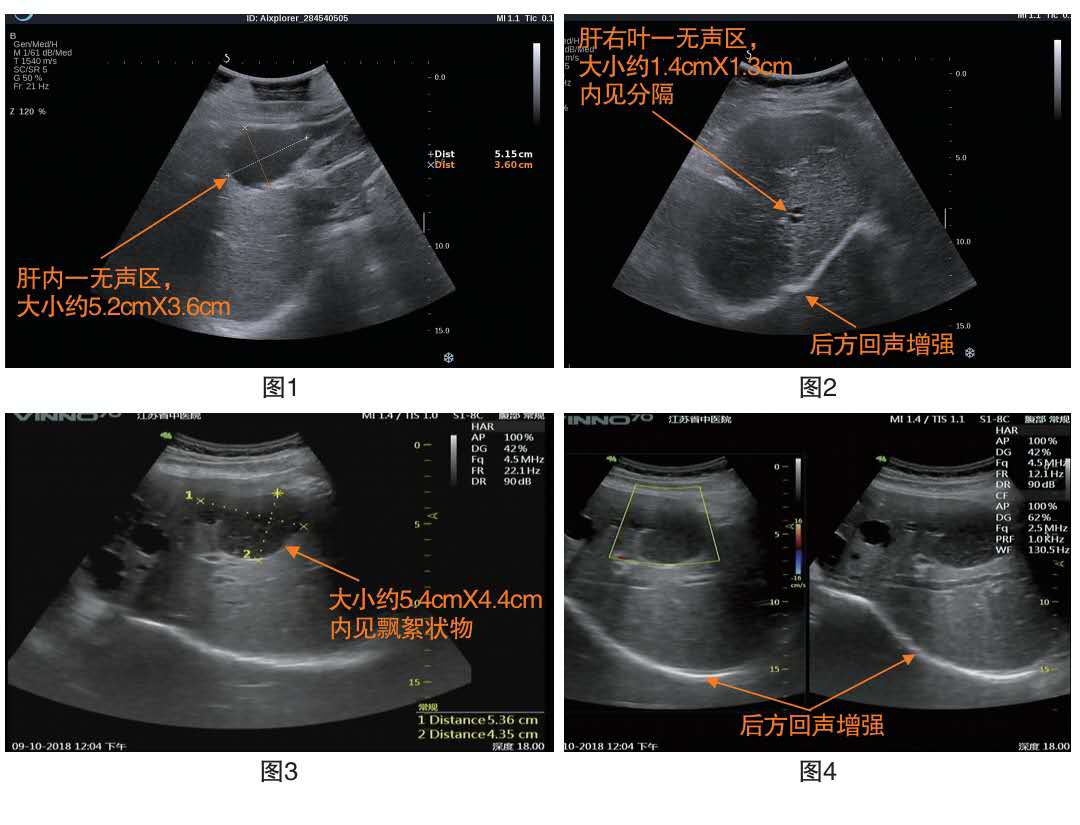

肝囊肿彩超

肝囊肿需要注意的几点